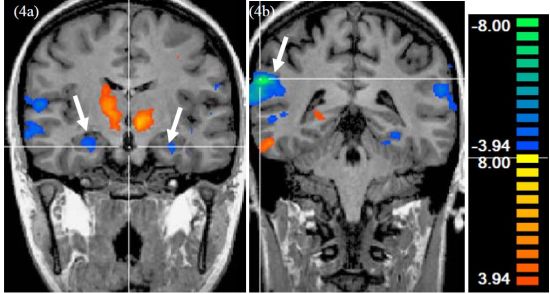

我们都知道大脑不同的区域对应着不同的功能。消费者在情感、决策等活动中,不同区域的脑电波信号会有所不同。譬如当我们很想拥有某件奢侈品时,大脑前额叶的第10视觉投射区将表现出兴奋,而这一区域通常与人们的自我认知和社会定位联系紧密。大脑扫描可以准确捕获到这种区别(如图)。

(图片来源:市场营销研究期刊Journal of Marketing Research 2009年2月刊)